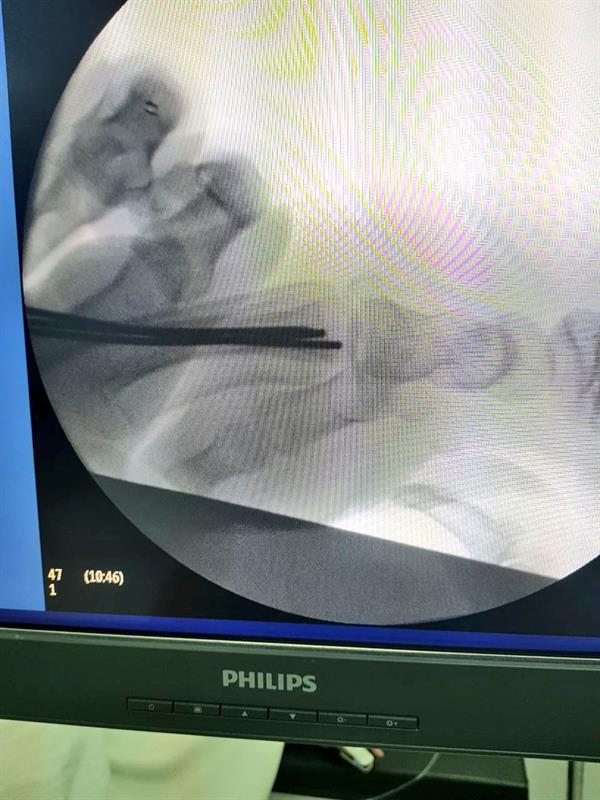

في مستشفى أبوعريش العام، تمكن فريق طبي متخصص من إجراء جراحة عاجلة ونادرة لطفل تعرض لحادثة مرورية نتج عنها خلع مشطيات اليد اليمنى بشكل كامل، حيث تم خلال الجراحة وإدخال الأسلاك المعدنية «IC.wires» من نهاية المشطيات عن طريق فتحات لا تتجاوز 2ملم وتثبيتها بالرسغ.